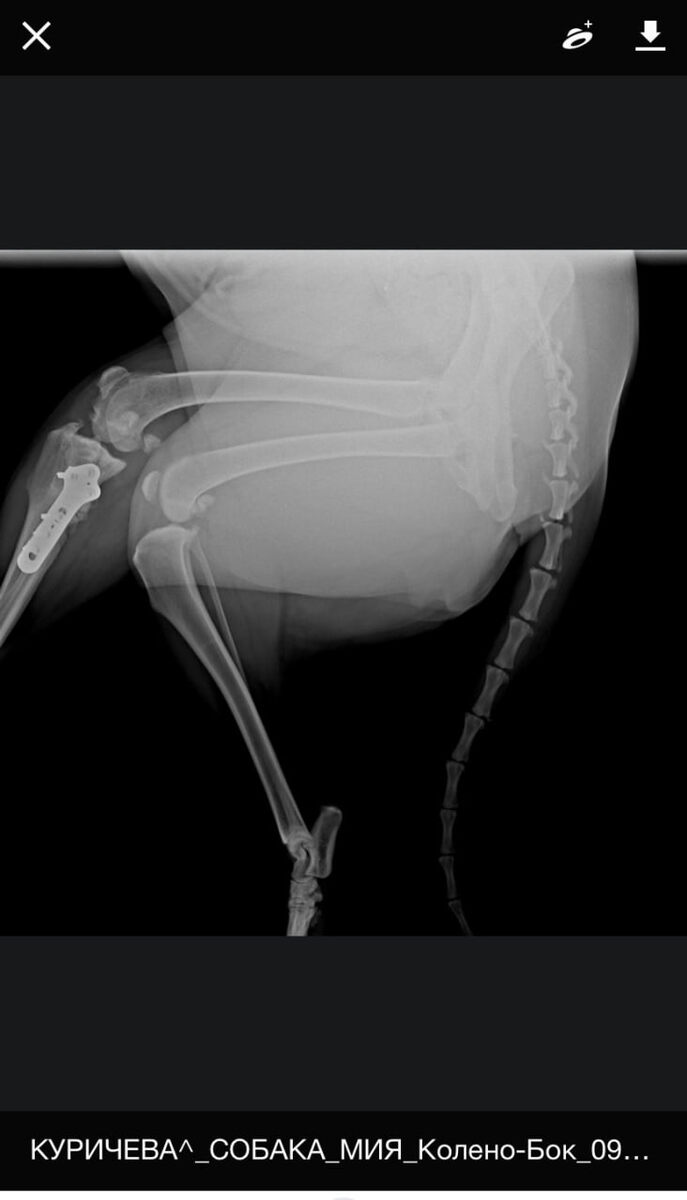

Лапка после операции восстановилась хорошо! Хирург проверил, сделал рентген — с пластиной всё в порядке. Слава Богу! 🙏🏼

Но артроз, к сожалению, не лечится и со временем прогрессирует. Однако можно немного затормозить процесс: